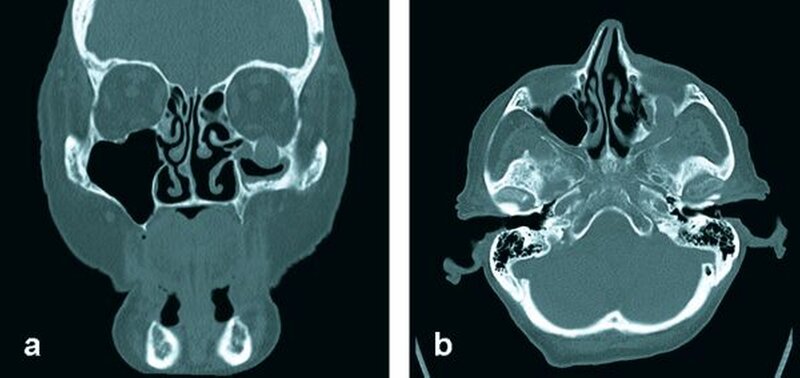

Bei Verdacht auf ein Rezidiv des vordiagnostizierten primitiven neuroektodermalen malignen Tumors wurde zur weiteren Abklärung im Rahmen des Restagings eine Computertomografie des Gesichtsschädels und des Halses veranlasst. Diese ergab einen ausgedehnten Tumor, der sich vom Wangenbereich entlang des Nervus infraorbitalis über die Fissura orbitalis inferior bis zur Schädelbasis wachsend darstellte. Der knöcherne Kanal des Nervus infraorbitalis zeigte sich massiv aufgetrieben (Abbildung 2). Die übrigen, im Rahmen des Stagings veranlassten Untersuchungen (Röntgen-Thorax, Oberbauchsonografie) ergaben keinen Hinweis auf das Vorliegen von Filiae.

In der Computertomografie und in der Kernspintomografie zeigt der pPNET keine spezifischen Muster, die Verwendung eines schichtbildgebenden radiologischen Verfahrens ist jedoch zur Bestimmung der Tumorausdehnung von Bedeutung [Luo and Xiao, 2008].